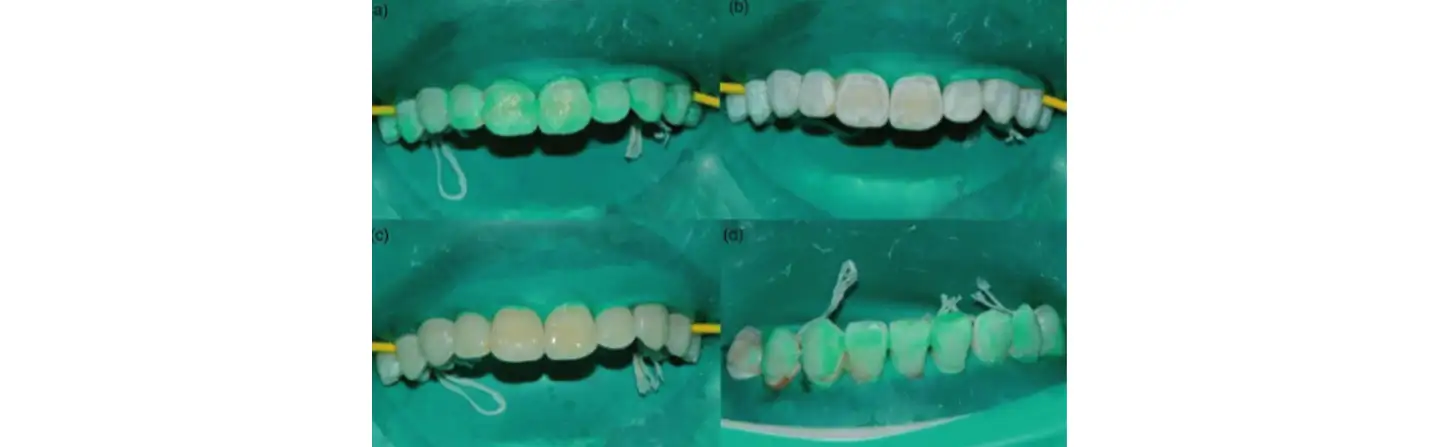

Процесс инфильтрации смолой